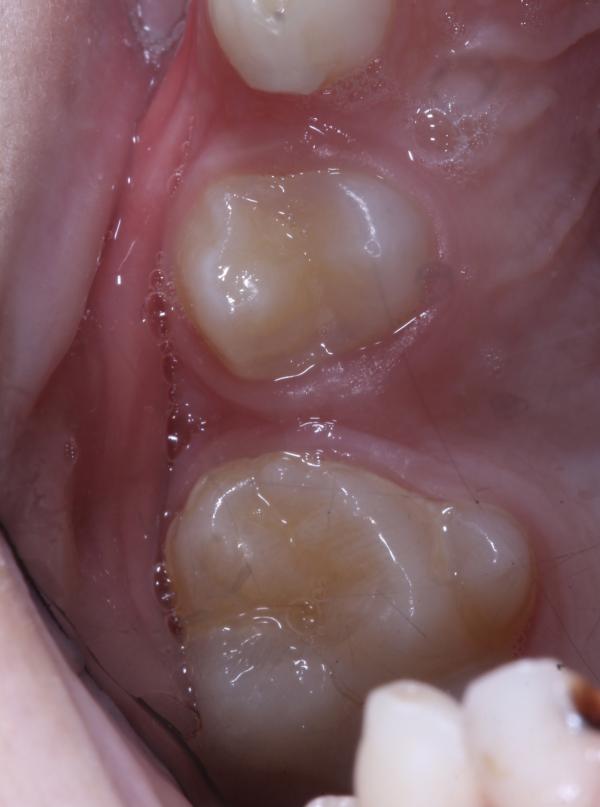

Теперь От слов «Зубы все равно молочные и они выпадут» у меня глаз дергается ☹️👁👁.

Я согласна что они выпадут , но выпадают они в своё время !!!

У каждого зуба своё место , свое время смены .

Знаете чем оборачиваются безобидные удаления зубов ???

Патологиями прикуса , бесконтрольным смещением 👣соседних зубов в сторону беззубого пространства 🦷.

Как это происходит ??

На втором фото один зуб занял место предназначенное для двух зубов (т.е один зуб остался в кости...